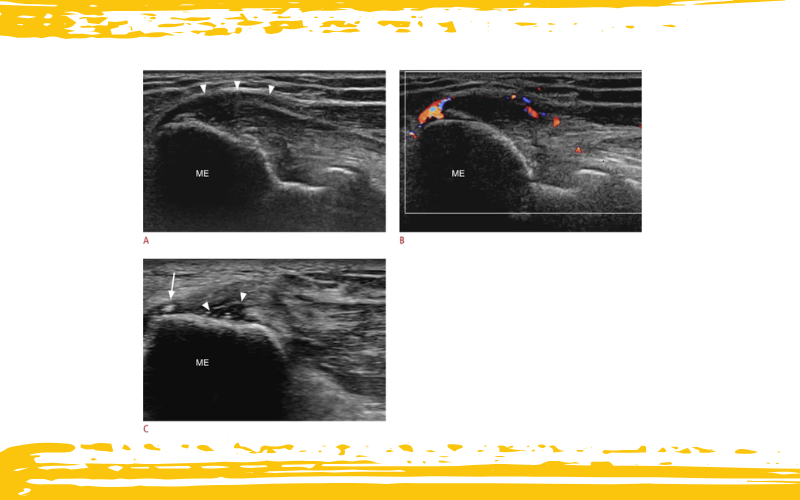

Hallazgos ecográficos (US) de la epicondilitis medial.

A. Las imágenes ecográficas en eje largo del codo medial en una mujer de 55 años revelan aumento de volumen, cambios hipoecoicos y abombamiento externo del tendón flexor común (puntas de flecha).

B. La imagen ecográfica Doppler de la misma paciente muestra neovascularización en el tendón.

C. La vista en eje largo del codo medial en un varón de 63 años muestra una pequeña calcificación (flecha) en el tendón flexor común y un área focal hipoecoica, indicativa de una pequeña rotura tendinosa (puntas de flecha).

ME: epicóndilo medial.

En eje largo, el tendón normal se visualiza como una banda continua de fibras longitudinales, homogéneas y altamente ecogénicas, que se extienden hasta la unión miotendinosa. Sin embargo, en la epicondilitis aparecen signos clásicos como:

- Cambios hipoecoicos focales o difusos

- Textura heterogénea y engrosamiento del tendón

- Contornos mal definidos y curvatura anómala hacia fuera

- Presencia de líquido subyacente

Además, pueden observarse calcificaciones intratendinosas (sólidas, con sombras acústicas posteriores), espículas de tracción o irregularidades en la inserción ósea. Estas calcificaciones suelen ser distróficas y bien delimitadas, a diferencia de las formas amorfas o quísticas más típicas de la tendinitis calcificada, que muestran una sombra acústica más variable.

El Doppler color o power Doppler puede revelar neovascularización, más frecuente en pacientes con síntomas prolongados. Es importante recordar que los vasos patológicos son fácilmente colapsables, por lo que no se debe aplicar presión excesiva con la sonda, ya que podría falsear la ausencia de señal doppler.

En cuanto a roturas, una rotura parcial se manifiesta como una hendidura anecoica o discontinuidad incompleta de las fibras. Aunque menos común, una rotura completa mostrará la pérdida total de continuidad y retracción del tendón.